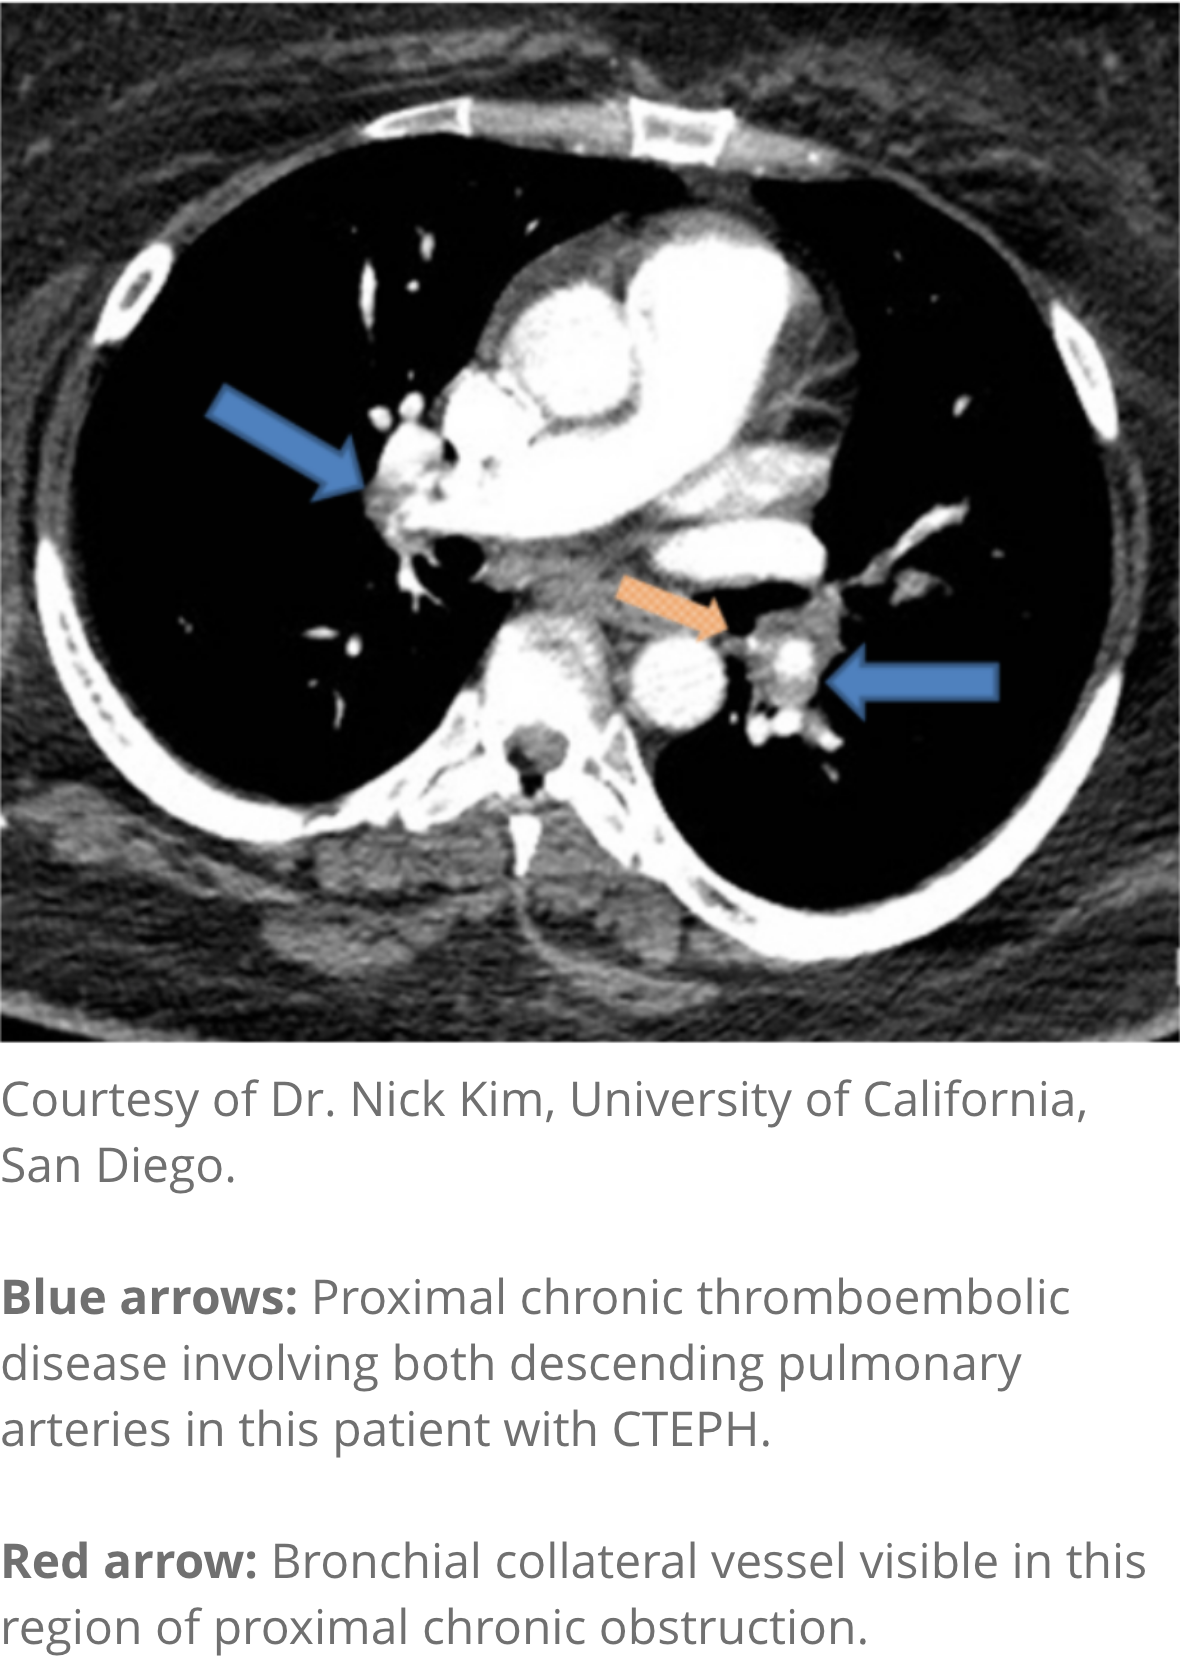

CT angiography

- Provides information regarding diagnosis and operability (eg, giving information on arterial walls)1,2

- Helpful in determining whether there is evidence of surgically accessible CTEPH1,2

- Note: Normal CT angiography does not exclude a diagnosis of CTEPH1,2